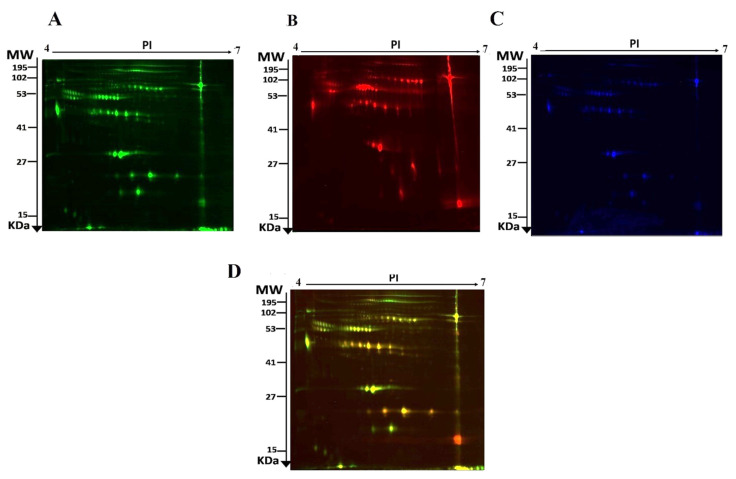

The current study assessed the difference in protein expression among 10 cannabis-exposed individuals and 10 controls (20 samples from 10 gels) using 2D-DIGE analysis technique before statistical analysis is performed with Progenesis software. Fluorescent protein profiles of a 2D-DIGE of control samples labelled with Cy3 are presented in Figure 1A. The CUD samples were labeled with Cy5 (Figure 1B), pooled internal control labeled with Cy2 (Figure 1C), and overlap of 2D-DIGE gels of samples labeled with Cy3/Cy5 (Figure 1D). A total of 1700 spots were identified on the gels, 156 were significantly different (ANOVA, p ≤ 0.05; fold-change ≥ 1.5) between the CUD and control groups (Figure 2). For alignment and further analysis, the spot patterns were reproducible across all 10 gels. The internal standard Cy2-labeled was included to perform normalization among the whole gels set in addition to the quantitative of the protein levels differential analysis. A total of 156 spots displayed a statistical significance among the two groups. These spots were manually excised from the preparative gel and underwent protein identification using MS.